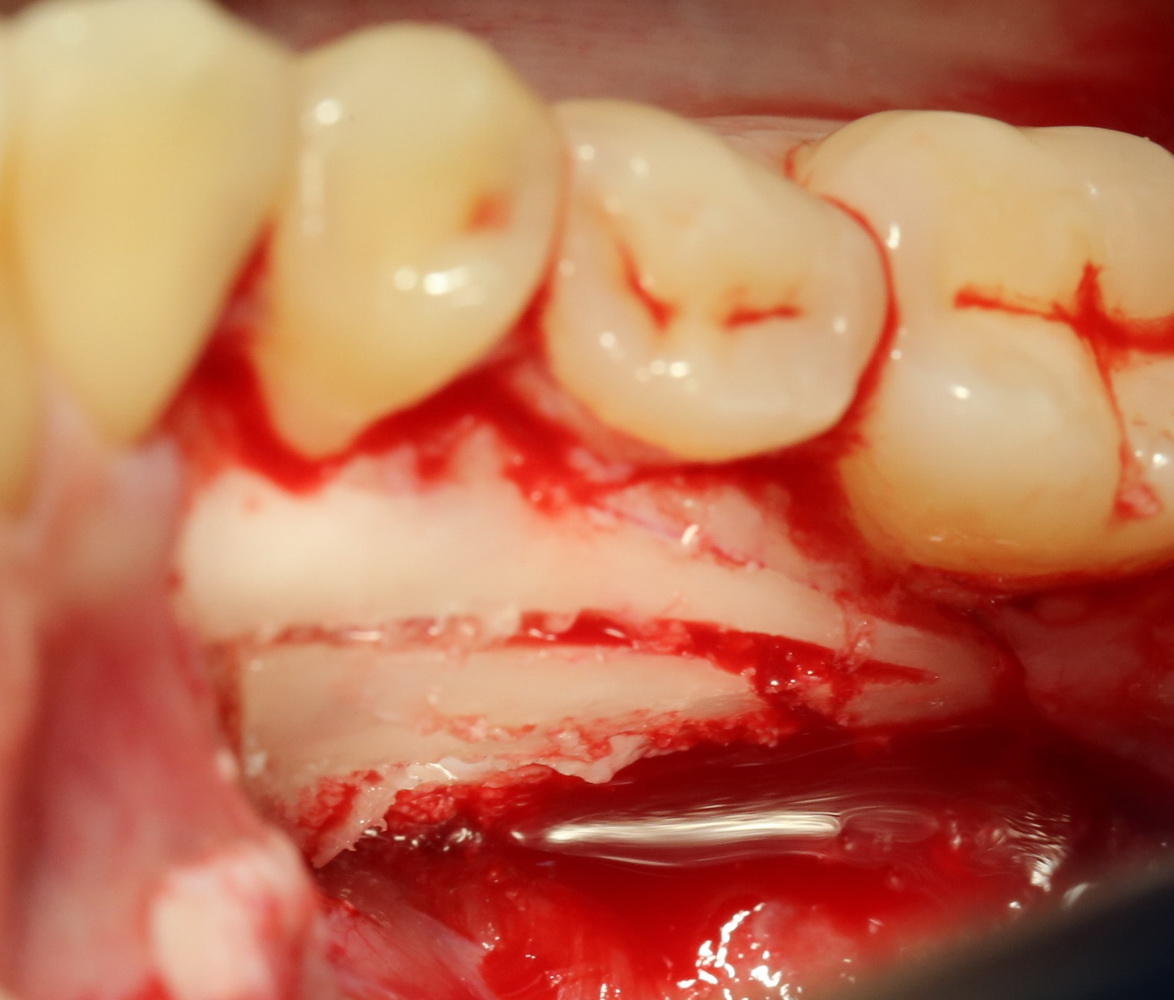

Итак, ультразвуковой разрез по костной ткани:

Костная «дверца» на время отделяется и убирается в физраствор, а мы видим следующее:

Это фолликулы и, частично, коронковые части сверхкомплектных зубов.

Теперь аккуратно нам нужно выделить сами зубы: